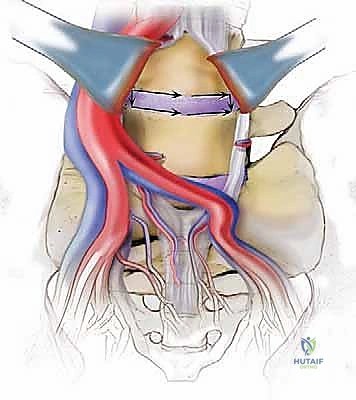

الخطوة 3: استئصال القرص (Discectomy)

بمجرد كشف القرص، يقوم الأستاذ الدكتور محمد هطيف بإزالة المادة الغضروفية التالفة بالكامل. يتم تنظيف الصفائح النهائية للفقرات (Endplates) العلوية والسفلية بعناية فائقة للوصول إلى العظم النازف، وهي خطوة حاسمة لضمان نمو العظم الجديد والتحامه.

الخطوة 4: التحضير وزراعة القفص (Implant Insertion)

يتم قياس الفراغ المتبقي بدقة لاختيار الحجم المثالي للقفص الجراحي (Cage). يُصنع هذا القفص عادة من مادة PEEK أو التيتانيوم، ويتم حشوه بمادة عظمية (طعم عظمي ذاتي من المريض، أو طعم صناعي، أو بروتينات محفزة لنمو العظم BMP). يتم إدخال القفص بقوة في الفراغ، مما يؤدي فوراً إلى استعادة ارتفاع القرص الطبيعي وتوسيع المخارج العصبية (تخفيف الضغط غير المباشر).